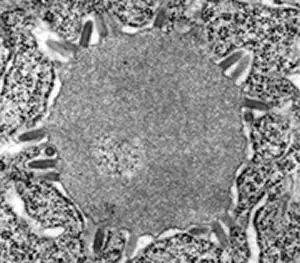

内基小体本质上是病毒的"工厂"。在这里,病毒的核衣壳物质大量聚集,正在进行活跃的复制。电子显微镜下的内基小体呈现出一种迷人的内部结构:中心是致密的病毒核衣壳颗粒,周围环绕着各种细胞器和病毒颗粒。有些内基小体中可以看到正在从细胞膜出芽的病毒颗粒。

这张电子显微镜照片展示了内基小体形成的早期阶段。病毒核衣壳物质开始在神经元细胞质中聚集,一些病毒颗粒正在从周围的细胞膜出芽。当这个结构长大到一定程度,就可以在光学显微镜下看到典型的内基小体。